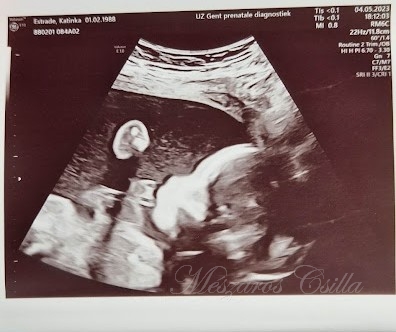

És aztán jött a válasz, hogy mindent megteszünk, kérünk egy napot. Szerdán befutott az első, majd a másik kórházból is a válasz, csütörtökön Gent-ben délután 2-re, Leuven-ben délután 4-re várják őket az orvosok. Megijedtek, most mi lesz, a két kórház kb. 100 km-re van egymástól, tuti nem fognak odaérni. De az én drága Katinkámat nem kellett félteni, veszteni valója nem volt. Írt ujra a kórházakba és tisztelettel megkérte őket, hogy tegyék lehetővé, hogy mindkét kórházba elmehessenek. Muszáj, hogy beszéljen velük, küzdeni akar és meg kell tudnia van-e esélye, értelme, tudják-e támogatni őt. Nem árult zsákbamacskát, elmondta, hogy ezt a két kórházat kereste meg. Nem sokkal később Gent-ből kapott üzenetet, hogy várják őket csütörtökön délután 2-re, menjenek, a többit majd ott megbeszélik.

Behívták őket a rendelőbe. Mindenki nagyon kedves, aranyos, mosolygós volt, ami nagyon feltűnt a másik kórházban tapasztaltakkal szemben. Katinka már éppen elkezdte mondani, hogy nekik 4 órára Leuven-be kell lenniük, mikor az orvos mosolyogva mondta nekik, ne aggódjanak, folyamatos konzultációban vannak a másik kórház orvosaival, sőt segitséget kértek külföldről is, a részletes dokumentációt és az orvosi tervet eljuttatják hozzájuk is később. Ha megfelel akkor Gent-ben fogják kezelni őt más orvosok támogatásával, segítségével, tanácsaival együtt.

Eleve ugy indítottak, hogy elmondták, kaphat kezelést a baba mellett, ami nem lesz káros a babára, viszont az ő állapotán javítani fog reményeik szerint. Elmondták, hogy mi ennek a menete. Minél előbb el kellene kezdeni a kezelést, szóval sok munka lesz a következő héten, egy kisebb műtét, mert ők május 15-én már szeretnék elkezdeni a kezelést. Szuper, mert Katinka és Vincent is ezt szerette volna. Elindult a versenyfutás az idővel… olyan emberek társaságában, akik az elkövetkezendő napokban, hetekben, hónapokban a mai napig bebizonyították, hogy az emberség, a kedvesség, a szeretet, az élet megőrzése mindenek felett a lényeg számukra. Tudásukat, tapasztalatukat egymás mellé tették, nem nagyképűsködtek, nem az önzőség győzött hanem összefogtak. Megértették Leuven-ben, hogy messze van, nem azért mintha nem vittük volna el minden alkalommal Katinkát oda is, de Gent itt van 15-20 percre. Bármi lenne, itt van a közelben, mivel ők sem tudták miként fog reagálni a kezelésre, a biztosra mentek, maradjon Gent-ben. Nem az volt a lényeg, hogy ők kezelhessék Katinkát, hanem hogy mielőbb a legjobb kezelést kapja ami csak lehetséges ezekben az időkben.